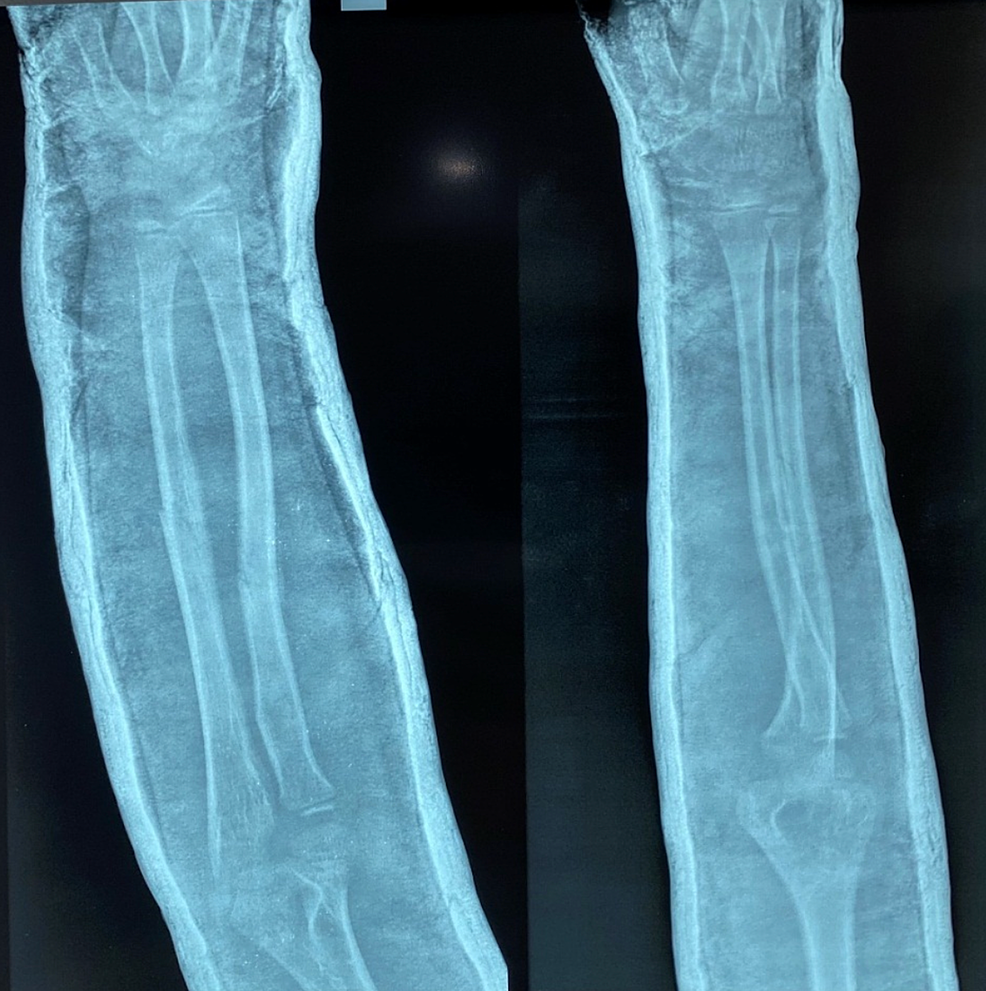

Pre-operative antero-posterior (AP) and lateral x-ray were taken (Figure 1). Adequate sedation was given to the patient. Fracture was reduced by the standard technique of axial traction manipulation. Reduction was confirmed radiologically by image intensifier and if found satisfactory, cast application was done (Figures 2, 3).

Antero-posterior (AP) and lateral view x-rays were recorded at two weeks post-reduction (Figure 5) and if no re-displacement was found, the cast was kept for four to six weeks and repeat radiographs were taken at four and six weeks and cast was removed (Figure 6). Radiographs were assessed for any angulation of the union site to assess for malunion. Clinical examination was performed three and six weeks after the removal of cast to assess the movement of the elbow and forearm. Stiffness of the elbow joint was assessed. The results were compared with the results of previously published results of casting of forearm fractures in flexion to determine the efficacy of casting.